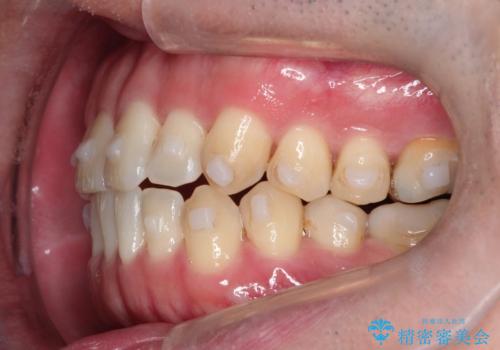

- 前歯の咬み合わせが気になるとのことで来院されました。

前歯が噛んでいない状態(開咬)のため、インビザライン矯正で改善することとしました。